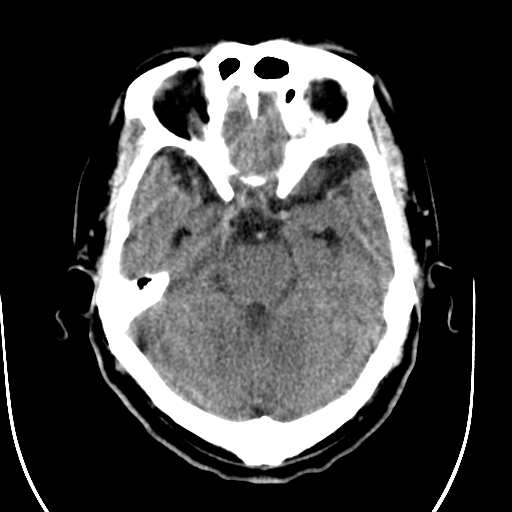

标题: CT28335:男,58岁,请各位看看是不是有脑积水,蝶窦内高密 [打印本页]

标题: CT28335:男,58岁,请各位看看是不是有脑积水,蝶窦内高密

1)脑积水。2)副鼻窦炎。